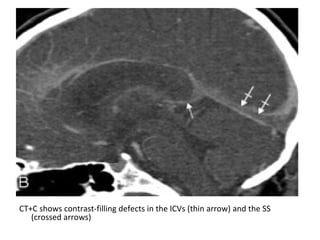

CT+C shows contrast-filling defects in the ICVs (thin arrow) and the SS

(crossed arrows)